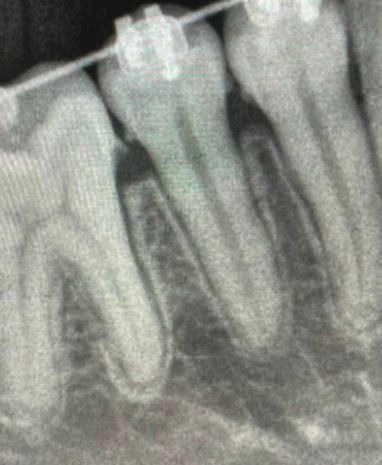

Raio-x Periapical e Bite-wing (interproximal)

Exame que mostra o dente completo e suas estruturas de suporte para diagnóstico preciso de alterações e infecções, e melhor vizualização de cáries.